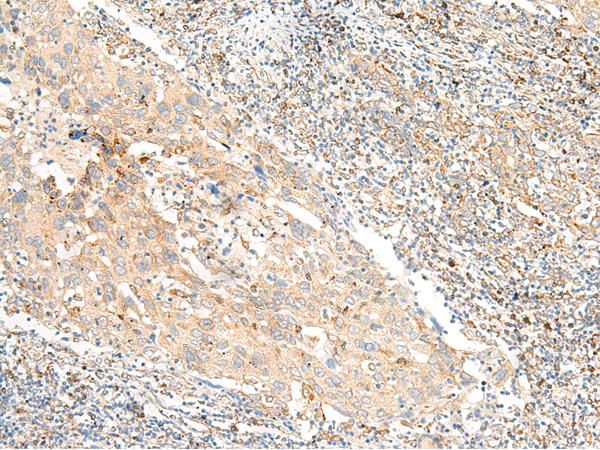

分类: 科研抗体货号: P06598别名:应用: IHC反应种属: Human, Mouse, Rat